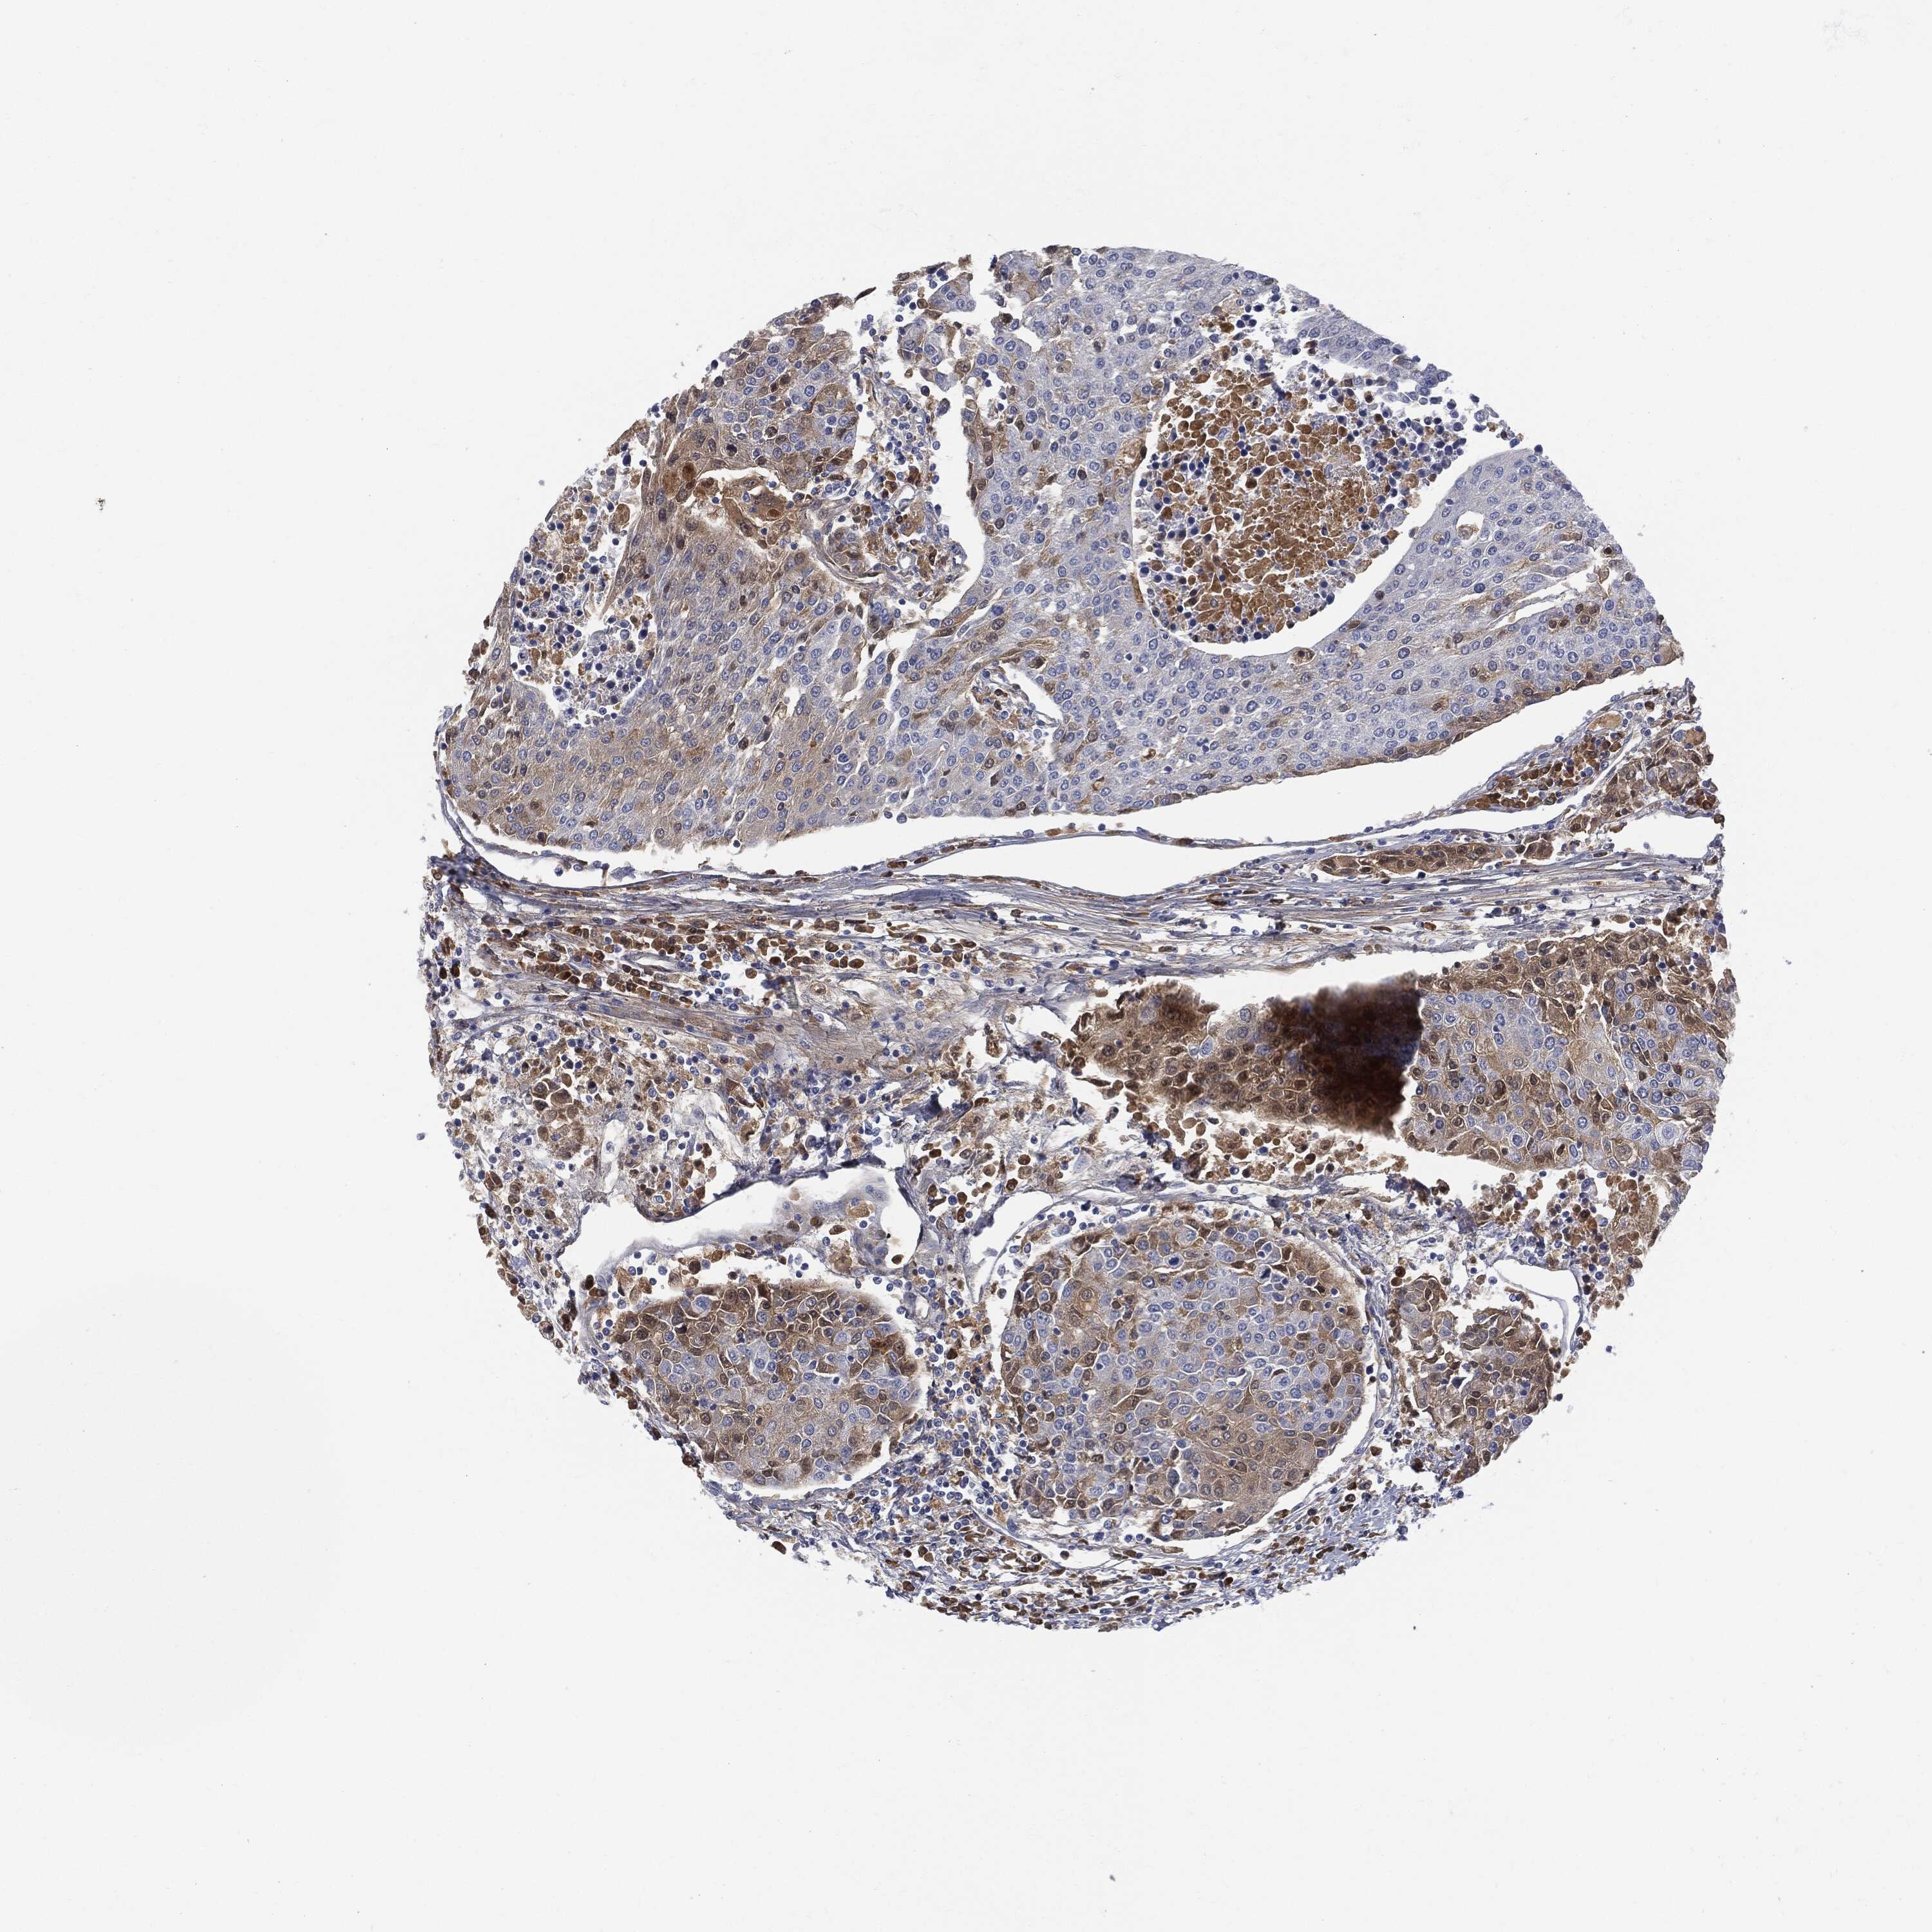

UROTHELIAL CANCER - Protein expressioni

A mouse-over function shows sample information and annotation data. Click on an image to view it in a full screen mode. Samples can be filtered based on level of antibody staining by selecting one or several of the following categories: high, medium, low and not detected. The assay and annotation is described here.

Note that samples used for immunohistochemistry by the Human Protein Atlas do not correspond to samples in the TCGA dataset.

Antibody stainingi

Antibody staining in the annotated cell types in the current human tissue is reported as not detected, low, medium, or high, based on conventional immunohistochemistry profiling in selected tissues. This score is based on the combination of the staining intensity and fraction of stained cells.

Each image is clickable and will lead to virtual microscopy that enables deeper exploration of all samples and also displays staining intensity scores, fraction scores and subcellular localization as well as patient and tissue information for each sample.

Antibody HPA001198

Antibody HPA002028

Antibody CAB016689

Antibody CAB080300

Staining

High

Medium

Low

Not detected

Intensity

Strong

Moderate

Weak

Negative

Quantity

>75%

75%-25%

<25%

None

Location

Nuclear

Cytoplasmic/membranous

Cytoplasmic/membranous,nuclear

Urothelial carcinoma, High grade

Urothelial carcinoma, Low grade

Adenocarcinoma, NOS